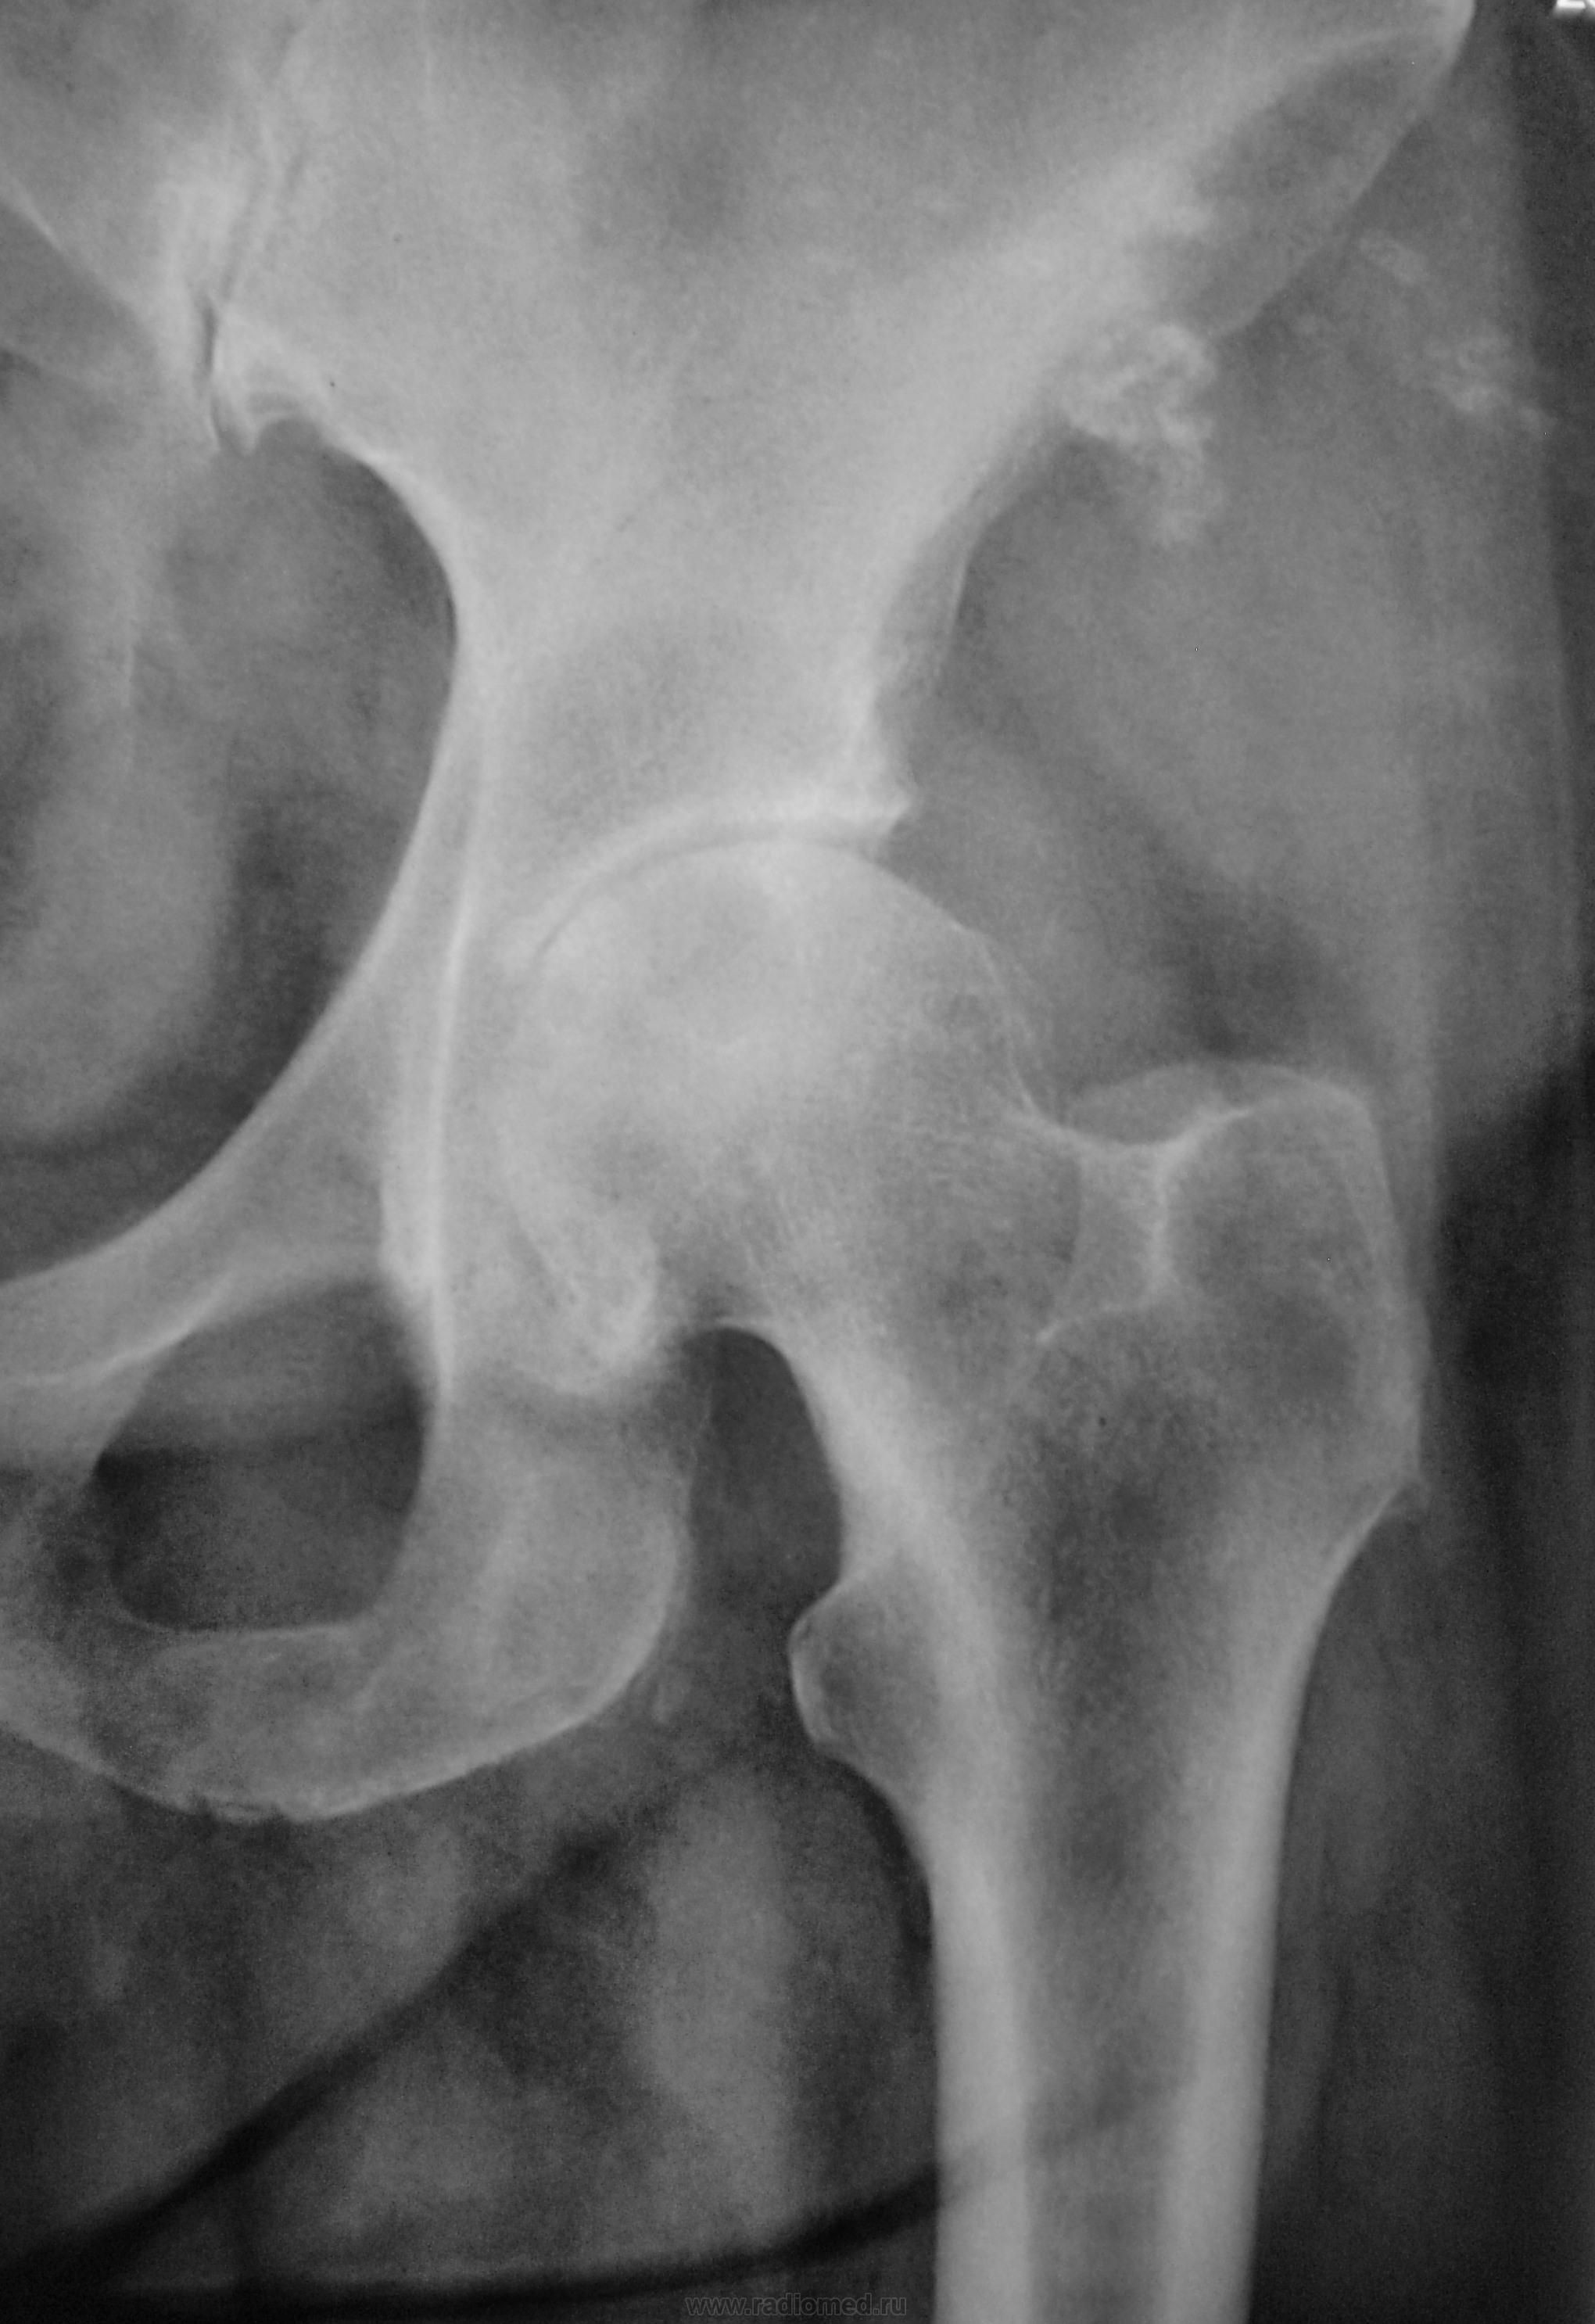

Крупный мягкотканный + компонент с атрофией, - объемом и склерозом контура прилежащей подвздошной кости, с бесформенными очаговым оссификатами параоссальной зоны. В ТБС помимо картины артроза (сужение щели, склероз, остеофитоз) имеются также полости просветления головки, сочетанные с перфокальным остеосклерозом. Фиброматоз?

Так при ревматоидном артрите и околосуставной остеопороз есть и бахромчатость или изъеденность седалищных костей бывает , и клиника присутствует.. И крупные кистовидные просветления - туда же. В данном случае и проявления деформирующего артроза тоже есть . Дуэт - так сказать .

Коксартроз III ст. с кистовидной перестройкой метаэпифизов.

ДОА 3ст, пятнистый остеопороз, создающий впечатление наличия кистозных просветлений в головке БК. Остеохондропатия(?) ветви седалищной кости.

Головка в средней трети - с костными эрозиями . Ревматоидный артрит 2 Rстадии?